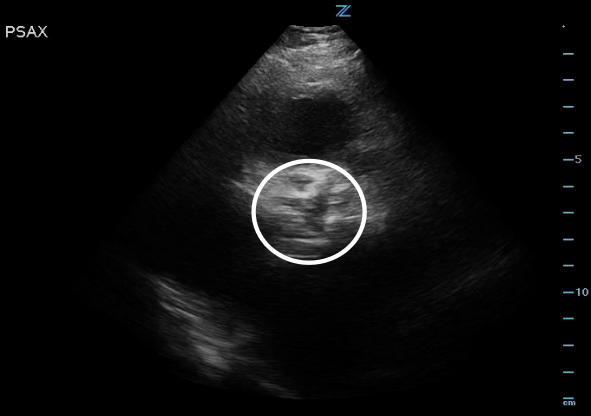

*Notice how calcified the AV leaflets are and how little the valve orifice opens.

Figure 2. High PSAX (RVOT) view of the AV orifice (circled) closed.

Figure 3. High PSAX (RVOT) view of the AV orifice (circled) open.